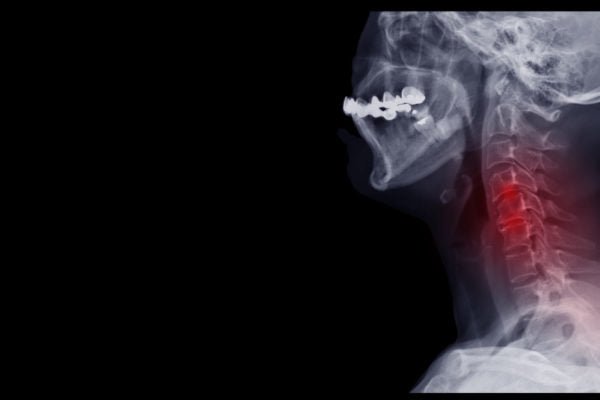

- Formación de Espuelas Óseas: El roce mantenido de los huesos puede llevar a que se formen osteofitos, que son "picos" en el hueso que pueden comprimir a los nervios que pasen cerca o causar molestias de otro modo.

- Estrechamiento del Espacio Interarticular: Primero perdemos el cartílago, y luego el hueso se va erosionando. Esto hace que el espacio intervertebral se reduzca, afectando a la movilidad del cuello y causando dolor.

- Evaluación Profesional: Tanto con pruebas objetivas (Como radiografías) como con las pruebas de fuerza y movilidad que podemos ejecutar sobre ti, podremos comprender mejor cual es tu condición específica, lo cual nos ayudará a saber cómo podemos ayudarte.